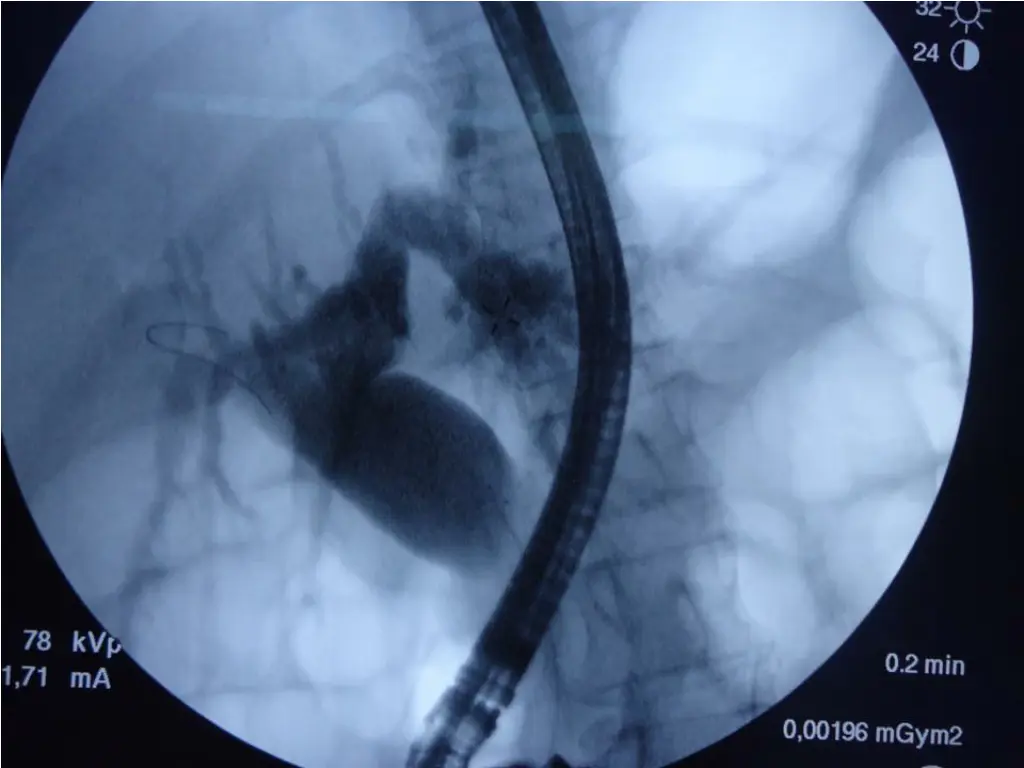

Test Result Hb 12.3 mg/dl WBC 15.3 PLT 654 U/L TSB 30.7 mg/dl D 29.5 mg/dl ALP 243 AST 75 ALT 83